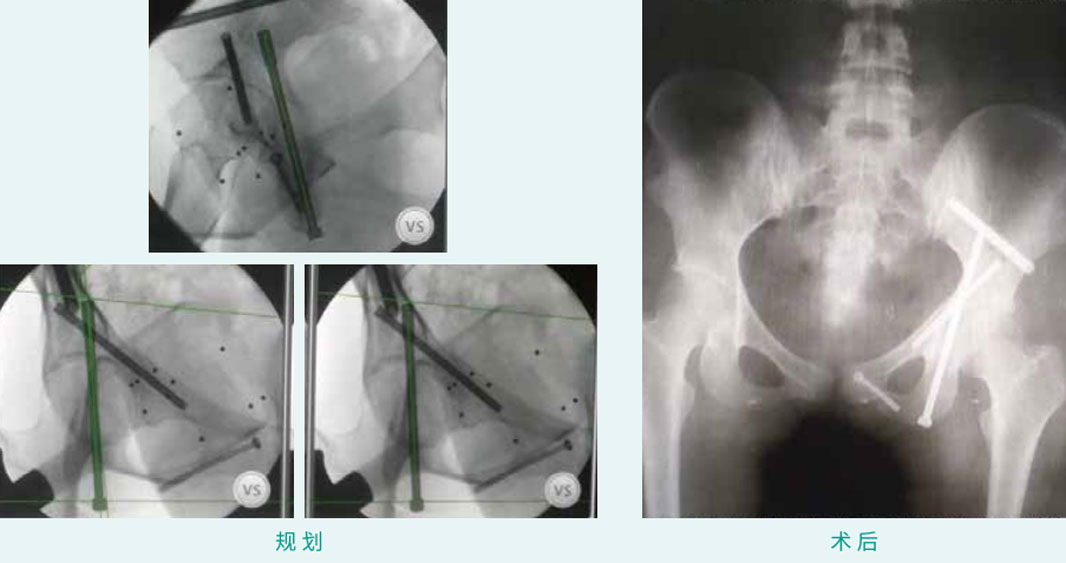

天玑? 辅助骨盆通道螺钉(前柱、后柱、耻骨下,LC-2型)经皮空心螺钉内牢靠术

基本情形:患者女,20岁,骨盆髋臼骨折

机械人累积用时:45分钟

植入物:4枚空心螺钉

病例泉源:天津医院 贾健 田维